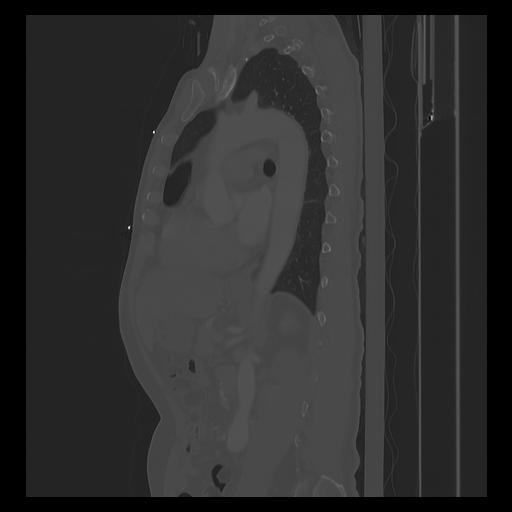

33 PULMON,CE,Sagittal,3.000,PULMON,Sagittal,